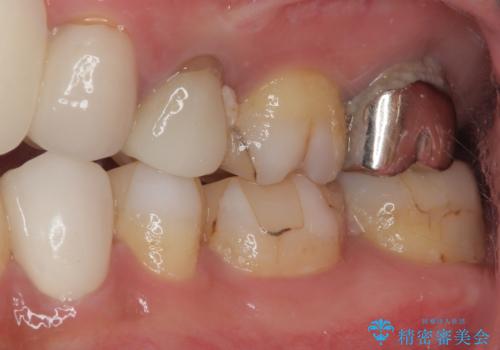

- 数日前から左下の奥歯がズキズキと脈をうつような痛みがあるとのことで来院された患者様です。

精査の結果、左下の第一小臼歯の虫歯が大きく進行していることが原因で痛みが出ていることがわかりました。

ラバーダム防湿を行ったうえで根管治療を行い、その後オールセラミッククラウンによる補綴治療を行っていくこととしました。